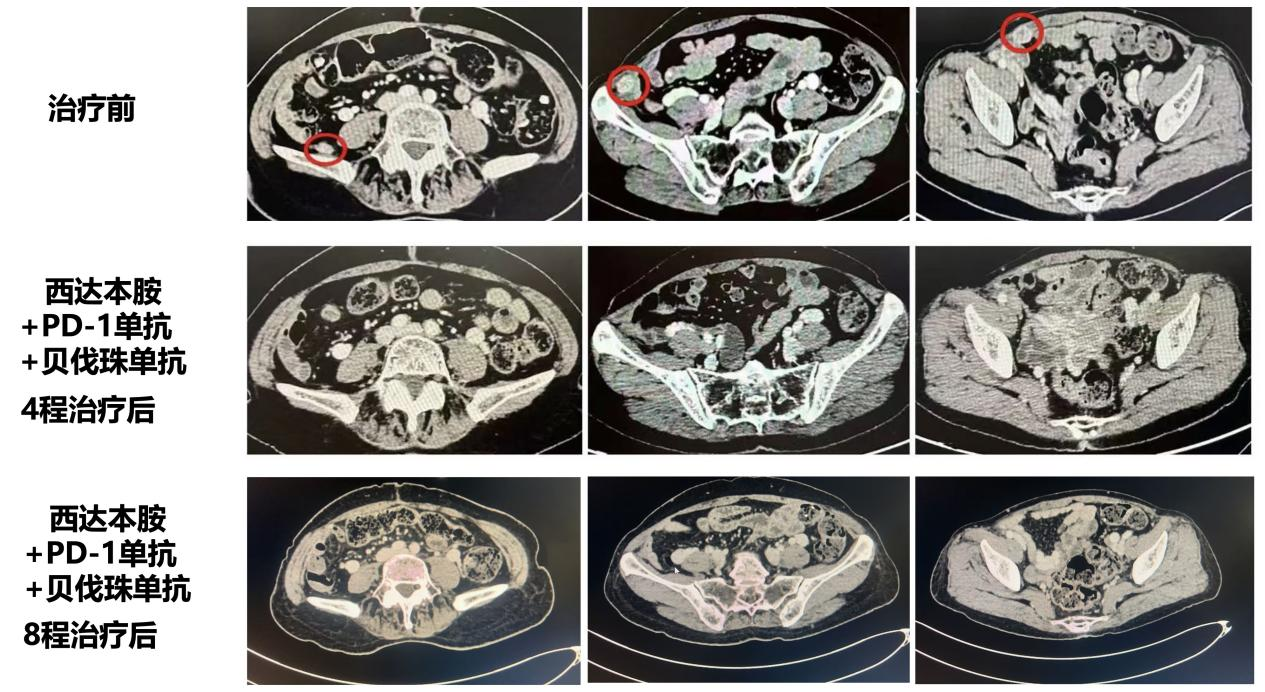

2025.08

4周期CAP方案治疗后,复查CT提示腹腔多发转移灶完全消失,疗效评价为CR,患者患者无明显不良反应。

2025.11

8周期CAP方案治疗后,复查CT提示腹腔多发病灶仍完全消失,疗效评价持续CR,,患者无明显不良反应。

图3 影像学评估